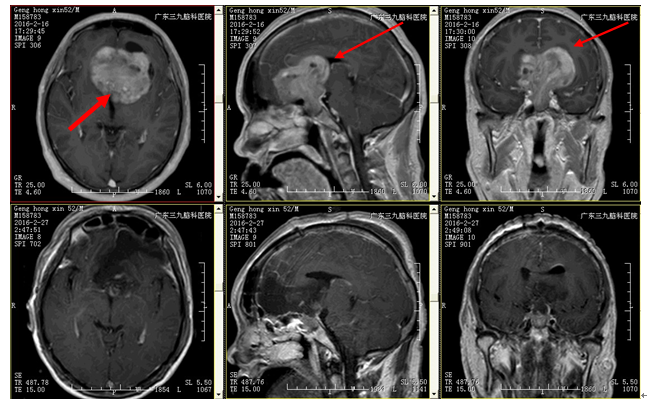

入院情况:神志清楚,正确对答以及遵嘱活动,双侧瞳孔等大等圆,对光反射灵敏,双眼眼球活动良好,粗侧颞侧缺损,左眼视力4.2,右眼5.1,四肢肌力5级,肌张力正常,生理反射存在,病理征阴性。辅助检查:外院头颅MRI平扫示:鞍区占位性病变,考虑垂体瘤可能性大。

诊疗经过:入院后予完善相关检查,查头颅CTA及MRI示:鞍区占位性病变,考虑垂体瘤可能性大,肿瘤血供丰富。向家属交代病情,诊断明确,有手术指征,告知术中术后相关风险后,家属表示理解并同意手术治疗。遂于全麻下行经额纵裂入路鞍区肿瘤切除+ICP探头置入术,术中可见肿瘤位于鞍区,血供丰富,边界清楚,质软,镜下予大部分切除肿瘤,术程顺利,术后予止血、抗感染、神经营养及补液等治疗,术后复查头颅CT、MRI示:呈术后改变,肿瘤大部分切除。术后病理结果回报:垂体瘤。